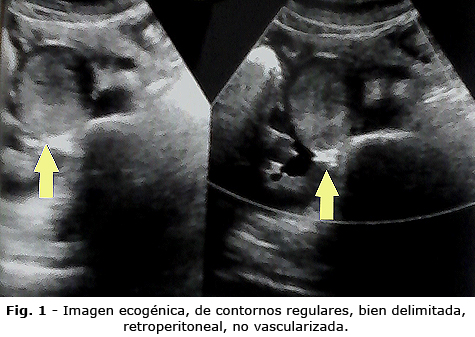

Sobre la base de los resultados anteriores se indicó una tomografía axial computarizada abdominal. Se realizaron vistas simples, y contrastadas con contraste yodado oral (Fig. 2). En el estudio simple se informó la presencia de una imagen nodular epigástrica, con contornos bien delimitados, de 75 unidades Hounsfield (UH). En el estudio contrastado se observó compresión del duodeno, de aspecto regular. Hubo buen paso de contraste al resto del duodeno y a las asas yeyunales, que eran de calibre y aspecto normal; páncreas de tamaño y aspecto normal, sin dilatación de las vías biliares extrahepáticas e intrahepáticas. Los demás órganos del abdomen superior estaban sin alteraciones. El músculo psoas era de tamaño y aspecto normal; el útero también era de aspecto normal.